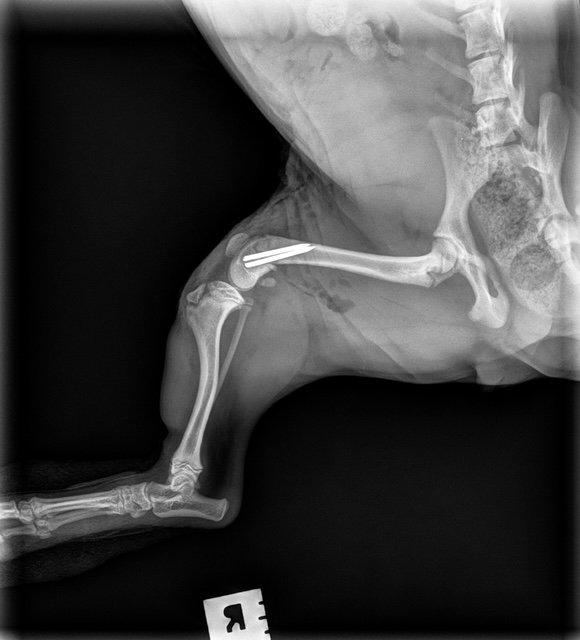

Extracapsular Repair (ExCap)

This procedure stabilizes the knee by placing a strong supportive material outside the joint to limit abnormal movement caused by a torn cranial cruciate ligament. The goal is to restore joint stability, reduce pain, and allow the surrounding tissues to heal and strengthen over time.

Extracapsular (ExCap) Repair #1

Extracapsular (ExCap) Repair #2